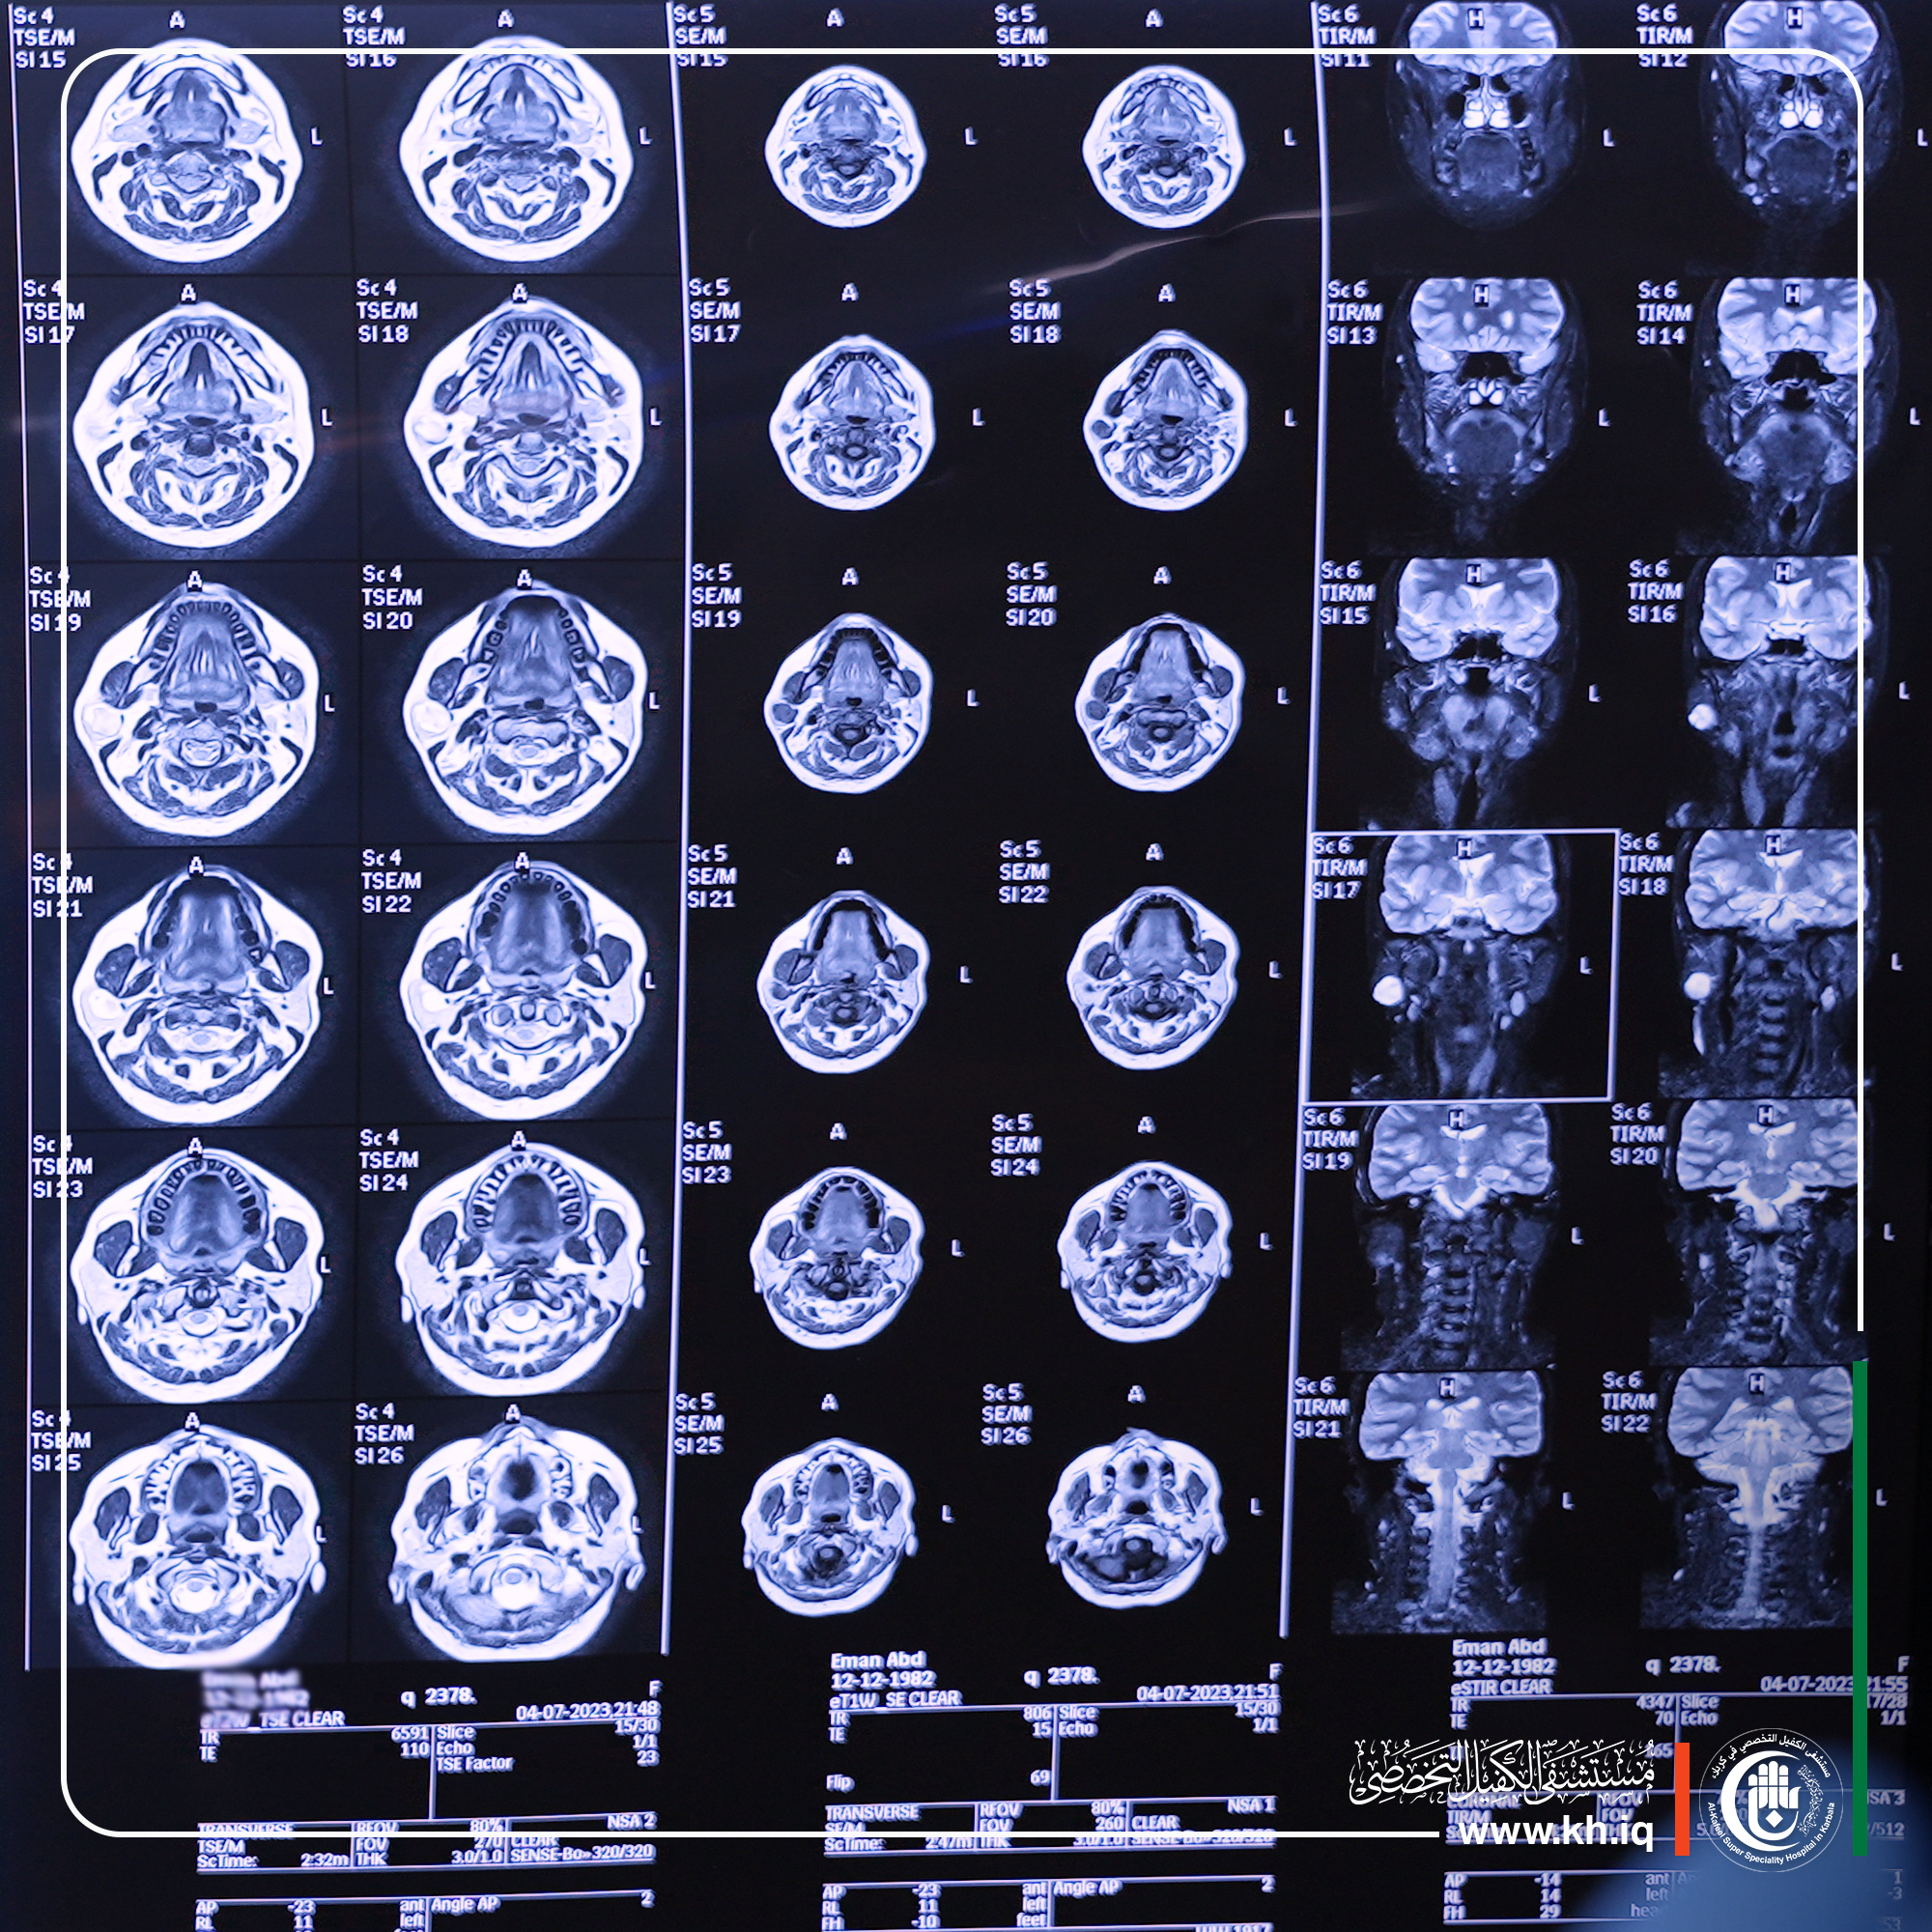

وقال اختصاصي جراحة الوجه والفكين د. رضوان الطائي، أجرينا عملية متقدمة لمريضة تبلغ من العمر ((40عاماً أحيلت لمشفانا وهي تعاني من تورم أسفل صيوان الأذن مبيناً بعد إجراء الفحوصات المختبرية والشعاعية عن طريق الرنين تبين وجود ورم في الغدة اللعابية النكفية من الجهة اليمنى على الطبقة السطحية مسبباً ضغط على عصب الوجه لذا ذهب قرارنا باتجاه العملية لتخليص المريضة من معاناتها.